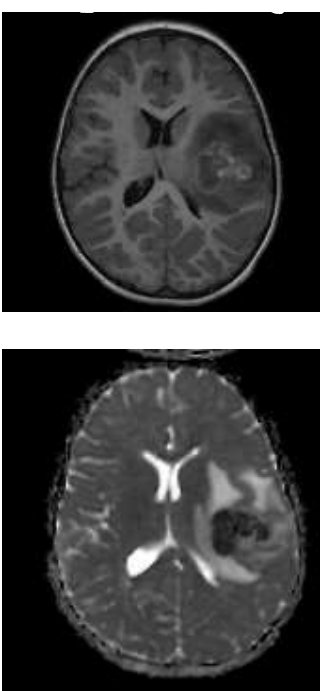

Sobre a lesão demonstrada no exame de ressonância magnética apresentado abaixo, assinale a alternativa que contenha o diagnóstico etiológico e a localização da lesão.